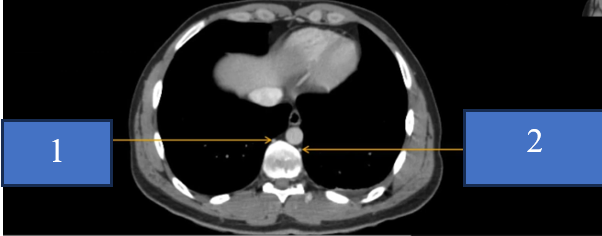

TM gan ở đâu? TM chủ dưới ? ĐM chủ?